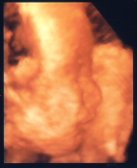

20030926

この前の検診で

お腹の赤子を3Dで見てきました。

↑ こーゆーのを想像してたんだけどさ

↑ お医者さんがお腹のデータを取り込んで

↑ 計算かなんかしてる間に私は起き上がり、

(寝たままだと見えないので)

↑ モニターに表示されたのを見ました。

↓ このような映像でした。